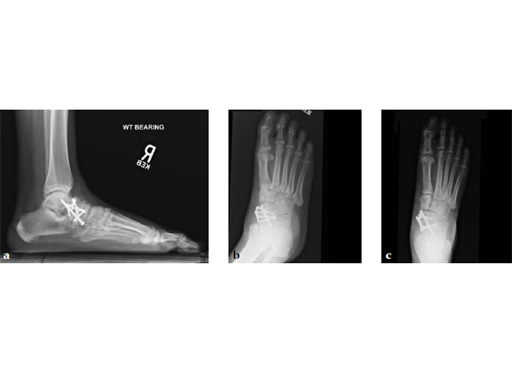

Case 5: First TMT, straight fusion and TMT fusion plates

A 46-year-old obese woman with coronary artery disease had sustained a Lisfranc injury while performing an exercise program. She was unable to weight bear and used an electric scooter.

In an effort to restore her ability to exercise and taking into consideration her body weight and upper extremity weakness, a decision was made to use the variable angle locking compression plate. These postoperative x-rays were obtained at 3 months, one month after beginning weight bearing. The patients pain was reduced and she was able to resume a progressive exercise program after 4 months following surgery.

Case provided by Michael Castro, Scottsdale, Arizona